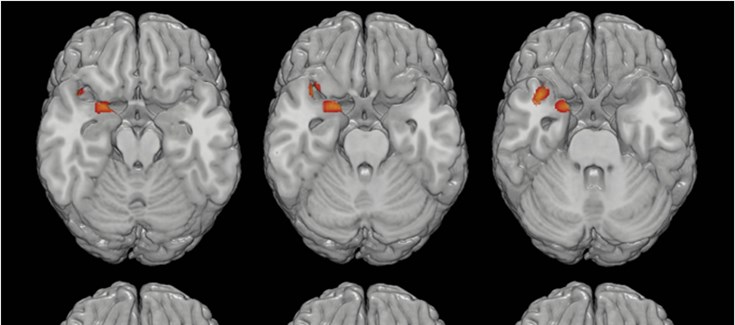

Según este estudio, el recuento de neutrófilos es más alto en los pacientes con PEP en comparación con los controles sanos y se evidencia una pérdida de materia gris asociada a esta cantidad, principalmente en las zonas del tálamo, ínsula, corteza entorrinal y giro temporal.

Los resultados del estudio ponen de manifiesto el papel de la desregulación inmune periférica en la enfermedad mental. A raíz de otras investigaciones, los autores proponen la presencia de neutrófilos en el tejido cerebral como biomarcador de la severidad de la psicosis, ya que parece ser uno de los principales desencadenantes de la perdida de volumen cerebral y del consiguiente declive clínico y cognitivo en estas enfermedades. También se abre la puerta a posibles tratamientos basados en bloquear la entrada de neutrófilos en el cerebro, aunque será necesario investigar más a fondo en esta línea para evaluar la viabilidad de este tipo de intervenciones.